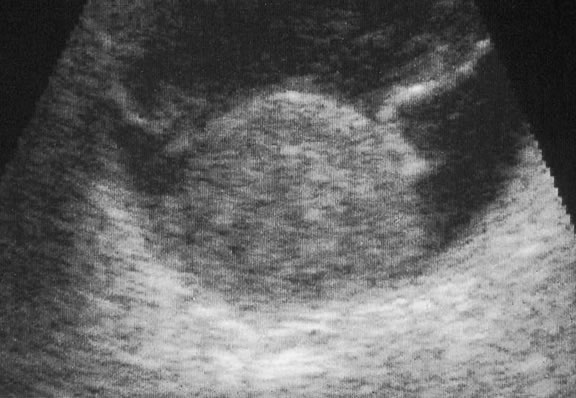

Ultrasonography can support the diagnosis of ciliary body or choroidal melanoma and is a particularly helpful way of disclosing tumors in eyes with opaque media.54 Ultrasonographic studies can alsodemonstrate areas of extrascleral extension. A scan ultrasonography shows a high internal spike and low internal reflectivity. B scan ultrasonography shows characteristic acoustic hollowness and choroidal excavation (Fig. 23). Hemangiomas and metastases usually appear acoustically solid because they contain multiple acoustic interfaces.

Fig. 23. B-scan ultrasound, choroidal melanoma.

The diagnosis of intraocular metastasis usually is made by slit lamp biomicroscopy and ophthalmoscopy in the patient who has been carefully questioned about a past medical history of cancer. Ancillary techniques such as intravenous fluorescein angiography and ultrasonography often can assist in making the diagnosis. Metastases generally begin to show hyperfluorescence in the late venous phase fluorescein angiography, somewhat later than most melanomas or hemangiomas.48,54 Metastases have many acoustical interfaces because they are composed of nests, cords, and island of tumor cells surrounded by stroma. Hence, they show high internal reflectivity on A scan ultrasonography and appear acoustically solid in B scan, characteristics they share with hemangiomas (Fig. 49). In cases in which the results from other studies are equivocal, cytopathologic examination of material obtained by fine-needle aspiration biopsy may establish the diagnosis.82,83

Fig. 49. B-scan ultrasound, choroidal metastasis. Placoid tumor has high internal reflectivity.